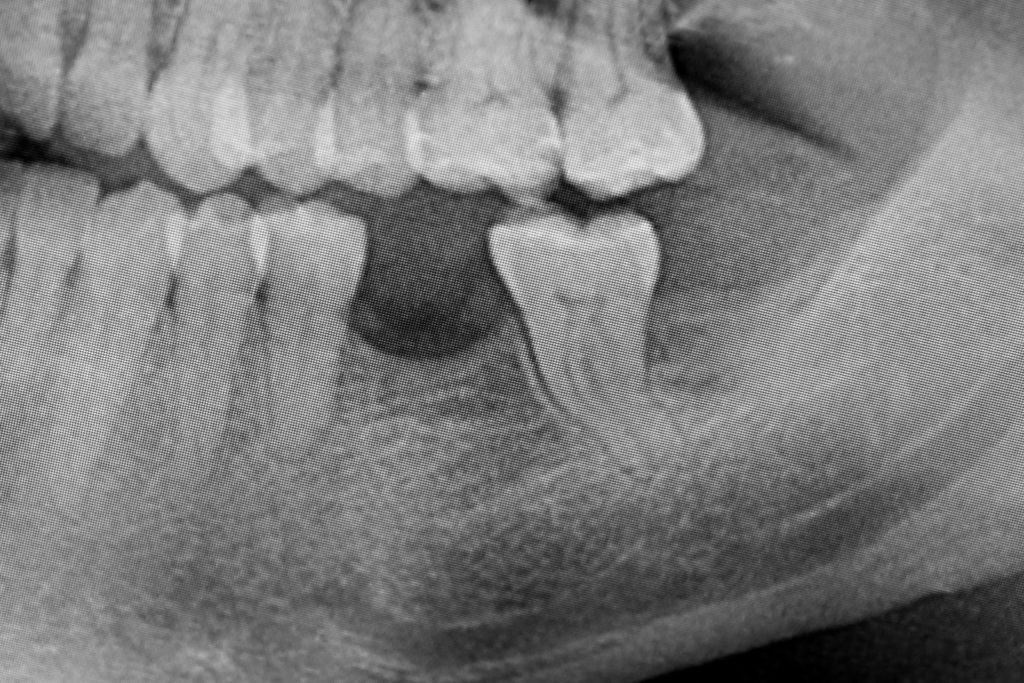

Przed podjęciem leczenia należy określić stopień zaniku kości szczęk oraz żuchwy. W tym celu przeprowadza się badanie kliniczne oraz odpowiednią diagnostykę obrazową pacjenta. Uwzględnia ona zdjęcie panoramiczne OPG jako podstawę dwuwymiarowego obrazowania podłoża kostnego oraz możliwe jest badanie tomograficzne CT lub bardziej precyzyjna tomografia stożkowa CBCT. Opcjonalnie wykorzystywana diagnostycznie tomografia pozwala na bardziej wnikliwą ocenę stopnia zaniku kości w trójwymiarowym, przestrzennym obrazie.

Zabieg odbudowy zębodołu powinno się wykonać możliwe jak najszybciej po usunięciu zęba. Jego celem jest odbudowa naturalnej objętości kości w miejscu utraconego zęba, a następnie szybkie wprowadzenie implantu. Najlepsze rezultaty uzyskuje się przy zastosowaniu biomateriału w formie bloczków kolagenowych lub granulatu, które dają trwałe efekty odbudowy oraz optymalną funkcję i estetykę odtworzonych koron zębów na wszczepionym implancie.

Procedury te są stosowane w sytuacji niedostatecznej ilości kości, skutkującej odsłonięciem gwintu, podczas gdy wszczepiamy implanty stomatologiczne lub też jako zabiegi poprzedzające ich wprowadzenie.​